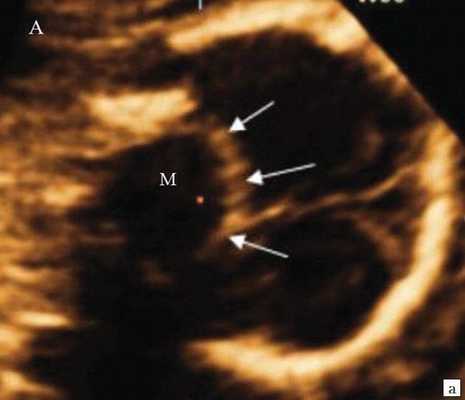

При изучении анатомии головного мозга плода в режиме 2D с применением стандартных аксиальных срезов во всех наших случаях мозжечок выглядел в виде овального образования однородной структуры с поперечным размером, менее уровня 5 процентиля для соответствующего срока беременности. При этом отсутствовала межполушарная выемка и область повышенной эхогенности по срединной линии мозжечка, характерная для отражения червя (рис. 1). На коронарном срезе также обращала внимание округлая однолобарная форма гипоэхогенного мозжечка (рис. 2). Использование трансвагинального подхода позволяло визуализировать дополнительно волокнистые структуры субарахноидального пространства (рис. 2).

Рис. 1. Аксиальные срезы головного мозга плода. Отражена картина однолобарного гипоплазированного мозжечка во всех наблюдениях.

а) Наблюдение 1.

б) Наблюдение 2.

в) Наблюдение 3.

г) Наблюдение 4.